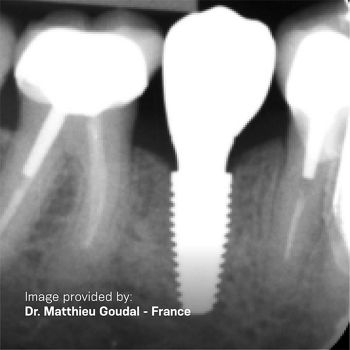

Grand Morse - La grandeza es un logro

Personalice sus tratamientos con confianza y aproveche los principios biológicos probados y fundamentos de la implantología dental.

El Helix® Grand Morse® le permite crear reemplazos dentales excepcionales para cada necesidad del paciente.

Tecnología del Sistema Grand Morse®

Tecnología del Sistema Grand Morse®